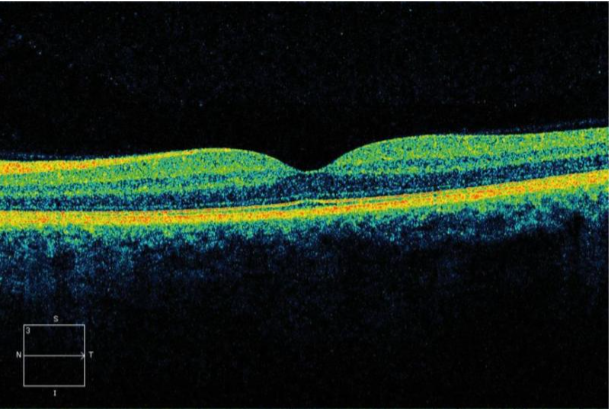

Resim 2: Yukarıda ki OCT görüntüsü normal makula yani sarı nokta görüntüsüdür.